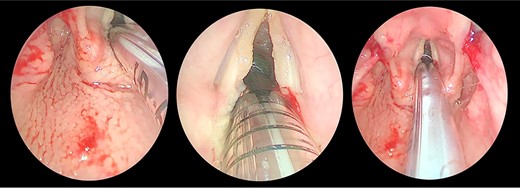

Transnasal flexible endoscope showing broad-based lesion affecting the middle two-third of the right vocal fold with a granular appearance of the interarytenoid region.

The patient maintained good oxygen saturation levels in room air with no signs of respiratory distress. She had a hoarse voice with a maximum phonation time of 10 s. Neck examination was unremarkable. Bedside transnasal flexible endoscope revealed bilateral vocal folds movement with polypoid lesions involving the middle two-thirds of the right vocal fold and the posterior part of the left vocal fold with edematous interarytenoid mucosa. Moreover, polypoid lesions were also seen in the base of tongue, epiglottis, with cobblestoning of the posterior pharyngeal wall (Figs 1 and 2). Basic laboratory tests were within the normal range. A contrasted neck computed tomography (CT) scan revealed bilateral asymmetric thickening of the vocal folds with medialization of the right vocal fold, with no enlarged cervical lymph nodes (Fig. 3).